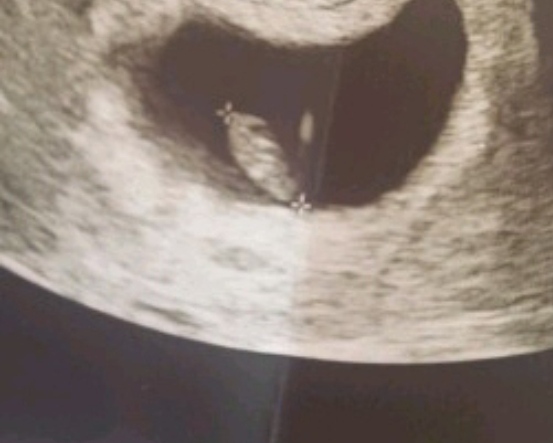

Banada bakabilirmisiniz karından 6+3Selamlar hayatım çok net değil ama tahminim var tabiki kız görüyorum umarım tutar sevgiler sunuyorum.

Resim bakmamız gereken kriterleri malesef karşılamıyor hayatım çok bulanık asla görünmüyor. Başka resim olduğunda yüklerseniz, tekrardan değerlendiririz.Banada bakabilirmisiniz karından 6+3